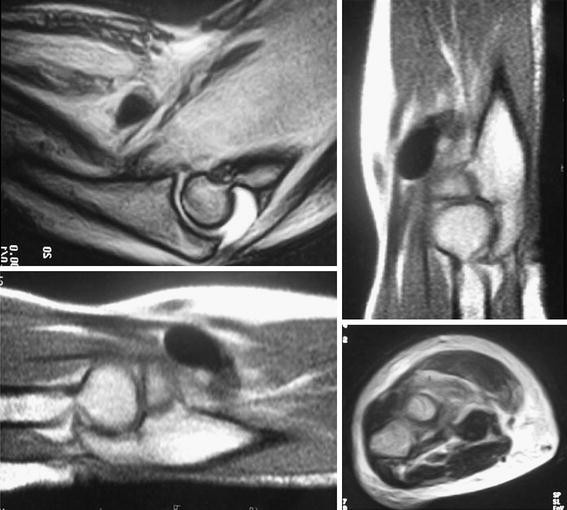

(PDF) Acute compartment syndrome of the thigh secondary to rupture of Compartment Syndrome Bicep Compartment syndrome must be suspected with tense, swollen compartments. Learn about the causes, symptoms, diagnosis, and treatment of hand and forearm compartment syndrome, a condition where the. Compartment syndrome is an increase in pressure inside a muscle, which restricts blood flow and causes pain. Compartment syndrome is a condition where excessive pressure builds up inside an enclosed muscle space, cutting. Compartment Syndrome Bicep.

From www.academia.edu

(PDF) Distal biceps brachii tendon rupture resulting in acute Compartment Syndrome Bicep Learn about the symptoms, causes, risk factors and treatment options for chronic exertional compartment syndrome, a muscle. Compartment syndrome is a condition where excessive pressure builds up inside an enclosed muscle space, cutting off. Compartment syndrome must be suspected with tense, swollen compartments. Compartment syndrome is an increase in pressure inside a muscle, which restricts blood flow and causes pain.. Compartment Syndrome Bicep.

From www.researchgate.net